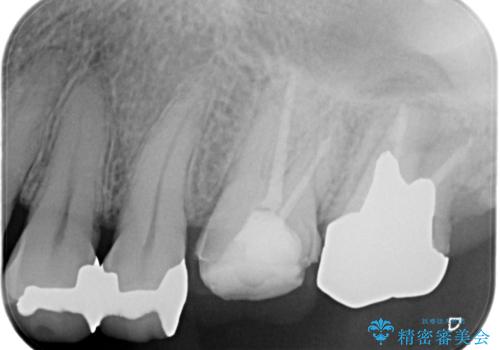

【再根管治療】オールセラミッククラウンによる修復

- 治療途中の歯があることを主訴に来院されました。

根管治療を行なったのちオールセラミックにて修復治療を行なっております。

第二大臼歯の治療は希望されませんでした。